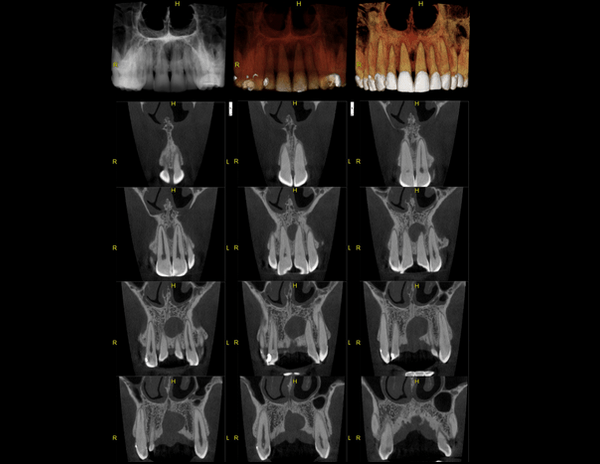

A Tomografia Computadorizada pela técnica do feixe cônico/cone beam (CBCT) introduziu um novo conceito de tomografia computadorizada na região bucomaxilofacial, que por meio da rápida aquisição volumétrica produz imagens com altíssimo grau de definição e fidelidade, além da redução na dose total de radiação emitida ao paciente.

Além disso, ocorre a minimização dos artefatos de imagem em relação à TC médica, o que torna possível a realização de imagens com qualidade diagnóstica e precisão sub-milimétrica, mesmo na presença de estruturas metálicas (restaurações, pinos/núcleos, aparelhos ortodônticos).